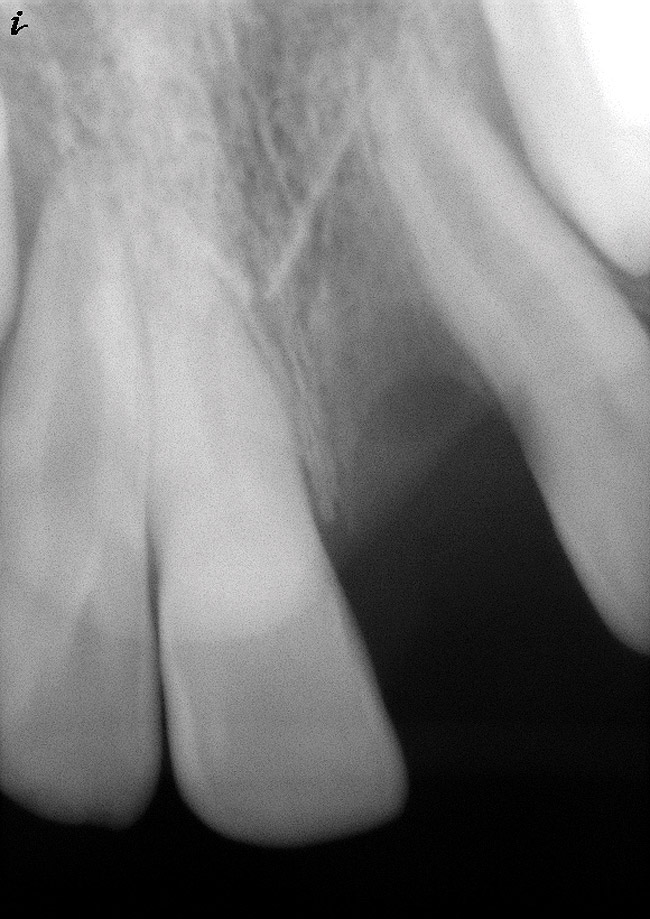

Figure 9  Clinical case of invasive cervical resorption that was deemed nonrestorable and the tooth removed.

Figure 9

Figure 10  Clinical case of idiopathic resorption of the upper second bicuspid. The tooth was deemed hopeless and extracted.

Figure 10